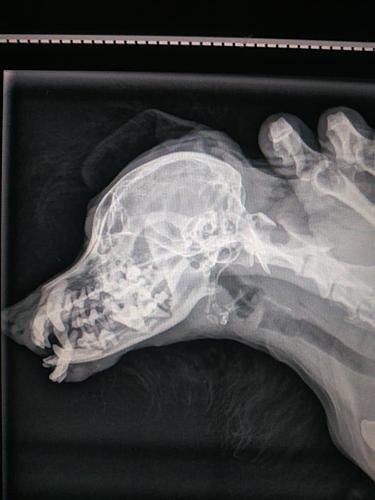

NO DIA 24 DE ABRIL, a Soneca foi mordida por um cachorro, com isso, além de quebrar/ moer o maxilar, ela quebrou todos os dentes e precisou fazer cirurgia de urgência ( Anestesista: 430,00; Odontologist: 950,00; Clínica+ consulta + exames + internação + centro cirúrgico: 950,00), esses valores já estão pagos.

Depois disso tudo, foi implantado um botão com fio para tentativa de reconstrução do maxilar. A cirurgia foi um sucesso. Voltamos ao Hospital Veterinário do Guarujá ( PONTO PET) e lá, falaram que ela precisaria de outra cirurgia para retirar o botão.